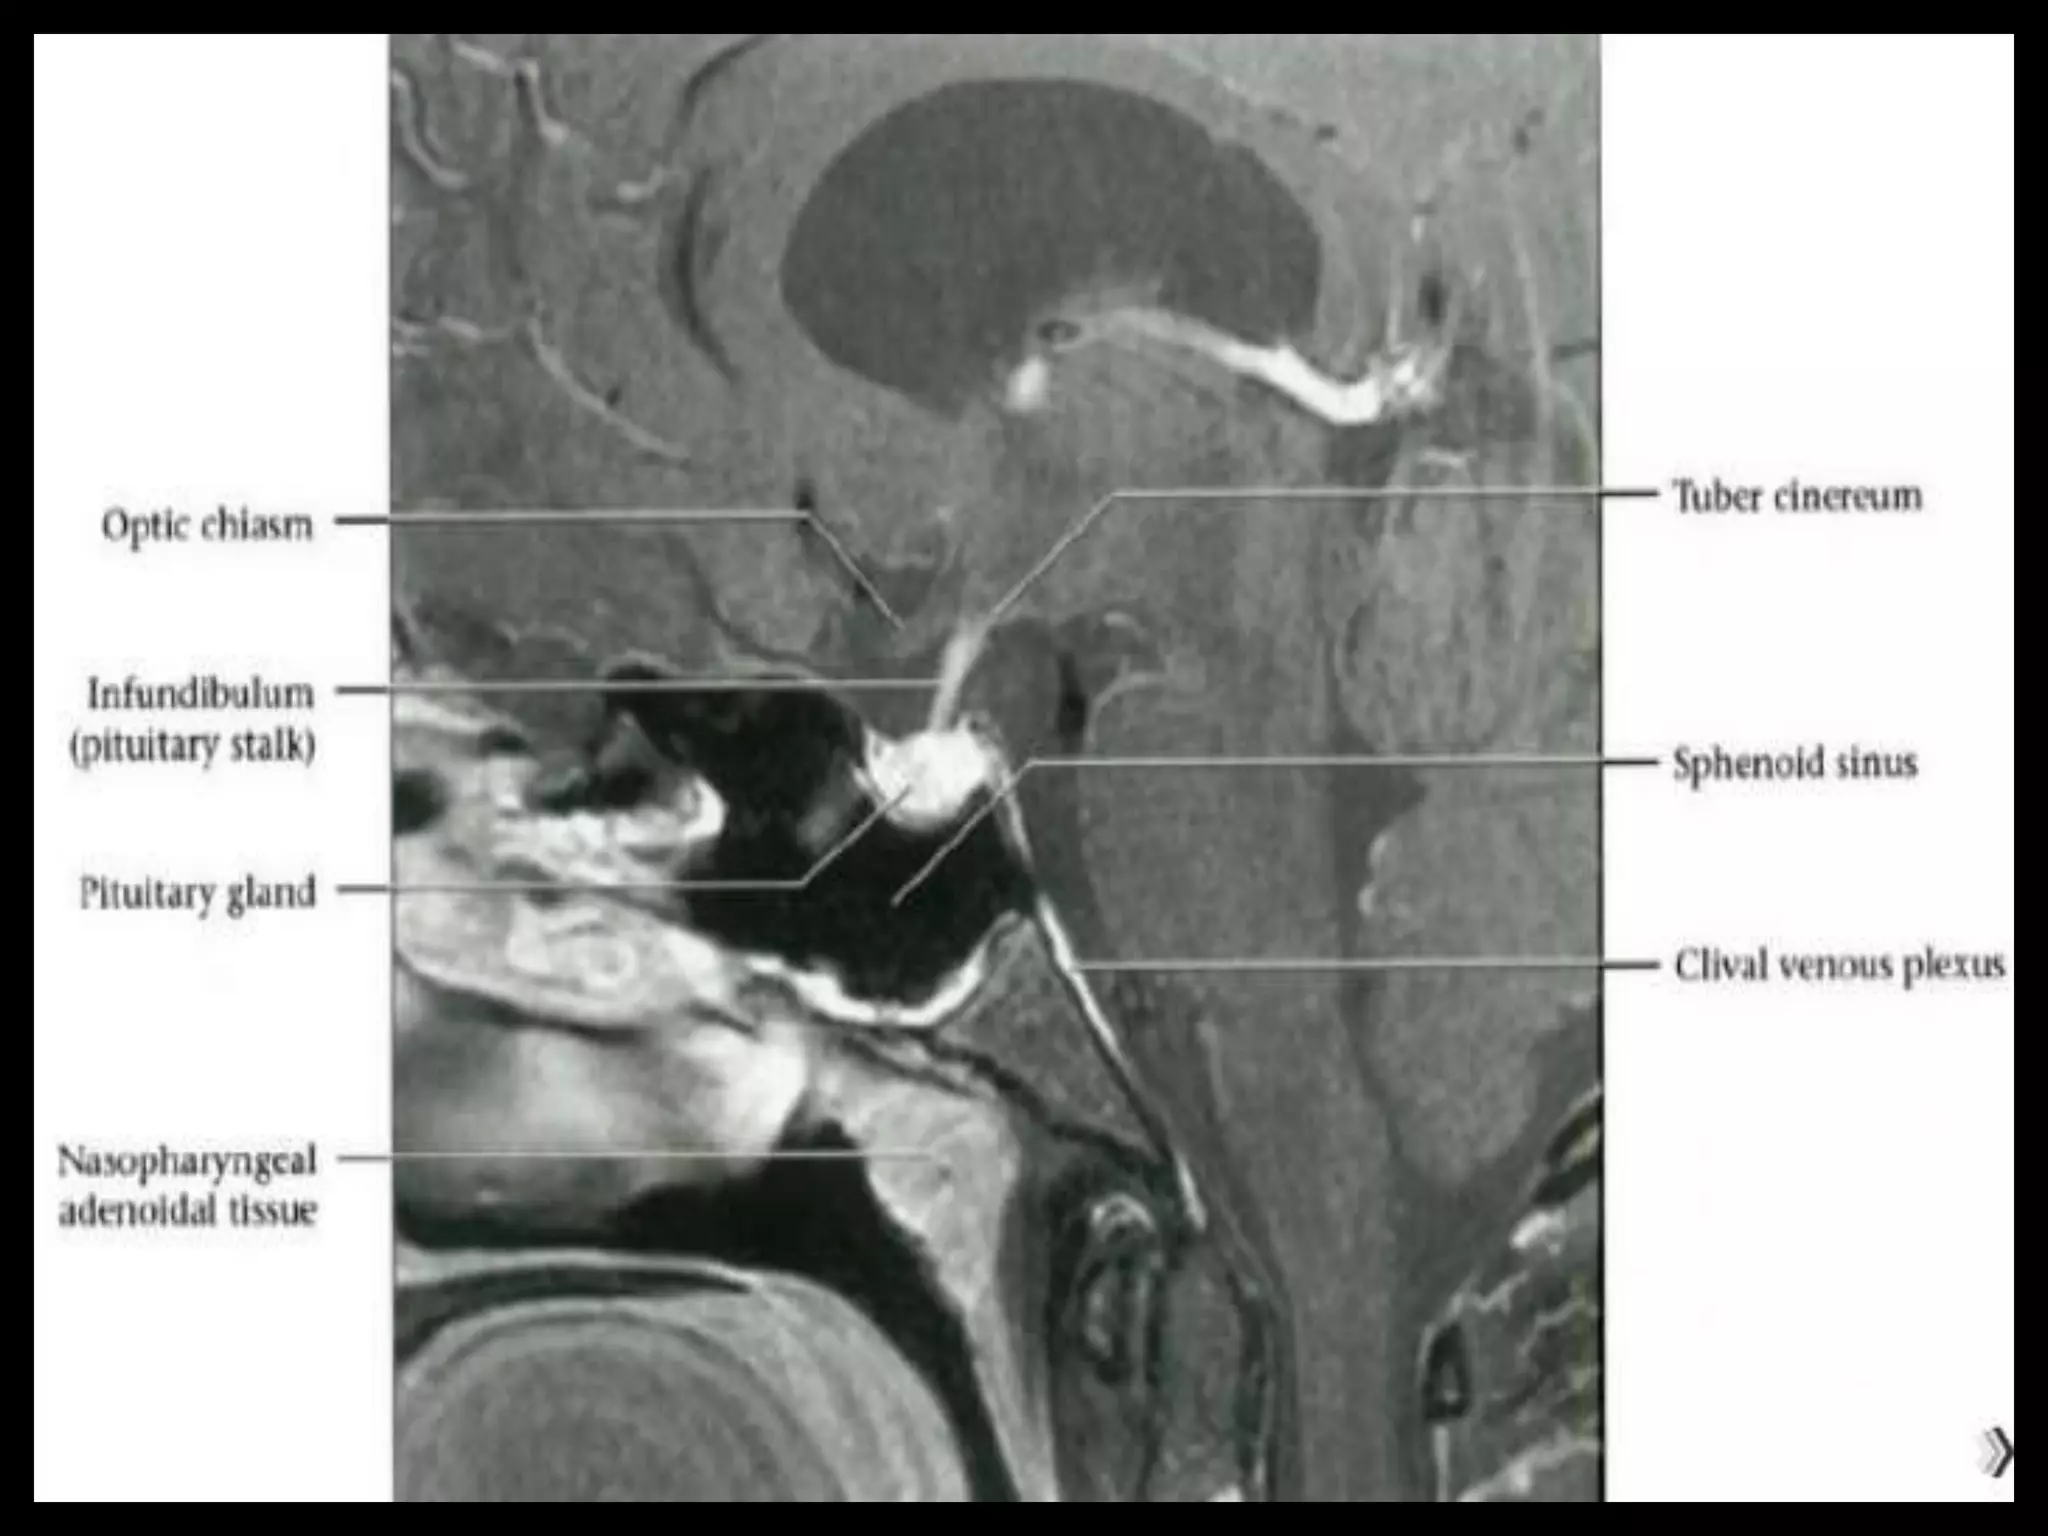

Pituitary Fossa.

Suprasellar Cistern

And Optic Apparatus.

Suprasellar Cistern AndOptic Apparatus.